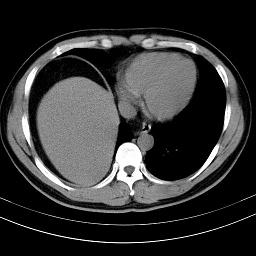

标题: CT18388:肝脏膈肌间隙内大量脂肪密度影 [打印本页]

标题: CT18388:肝脏膈肌间隙内大量脂肪密度影

考虑----气腹可能性大---进一步检查

是脂肪不是气体,有时候会碰到这样的病人,脂肪过多吧。

腹腔脂肪沉积过多

局部脂肪沉积。

膈下脂肪沉积。

考虑膈下脂肪沉积。

腹腔脂肪沉积症

激素治疗的病人容易脂肪沉积